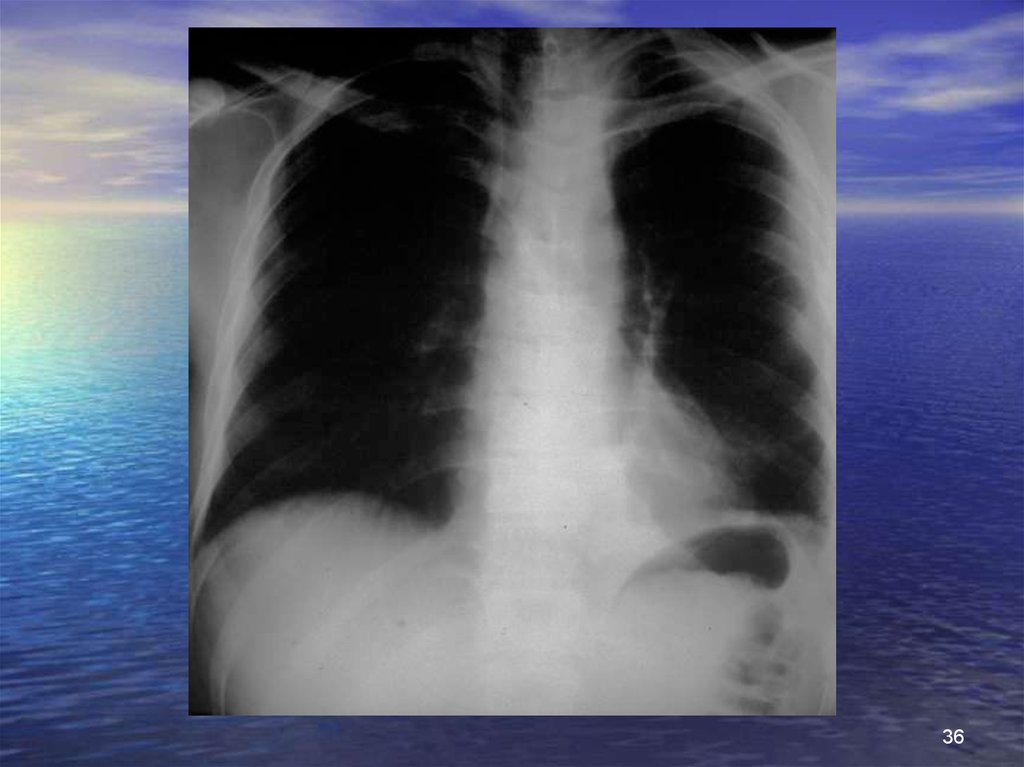

Признаки рентгенологические

Стандартный снимок грудной клетки

увеличение медиастинума +++ (камин),

понижение ствола корня легкого,

смещение трахеи вправо,

левосторонний гемоторакс,

исчезновение просветления аортолегочного пространства,

переломы грудины и/или 1-2 ребер

Ангиография

разрывы аорты: перешейка +++

аорты восходящей

аорты нисходящей

трещины или расслоение ствола брахеоцефального